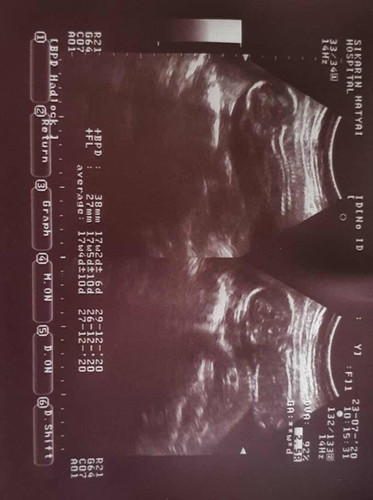

ใครพอมีประสบการณ์มั้ย ตอนนี้ 16 สัปดาห์แล้ว อยากทราบว่าได้ ผู้ขาย หรือผู้หญิง พอดี ท้องแรกค่ะ เลยดูไม่เป็น

นี่ไม่ใช่ส่วนที่ดูเพศค่ะ หมอไม่ได้บอกหรอคะว่าน้องเพศอะไร แม่ถามหมอได้นะคะ

ดูไม่ได้ค่ะ ต้องเป็นภากซาวด์หว่างขาไว้ดูเพศค่ะ

หมอถ่ายแต่กระดูกสันหลัง ดูเพศไม่ได้

ไม่ใช่ภาพหว่างขาค่ะ ดูไม่ได้

ในรูปไม่ใช่ส่วนเพศค่ะ